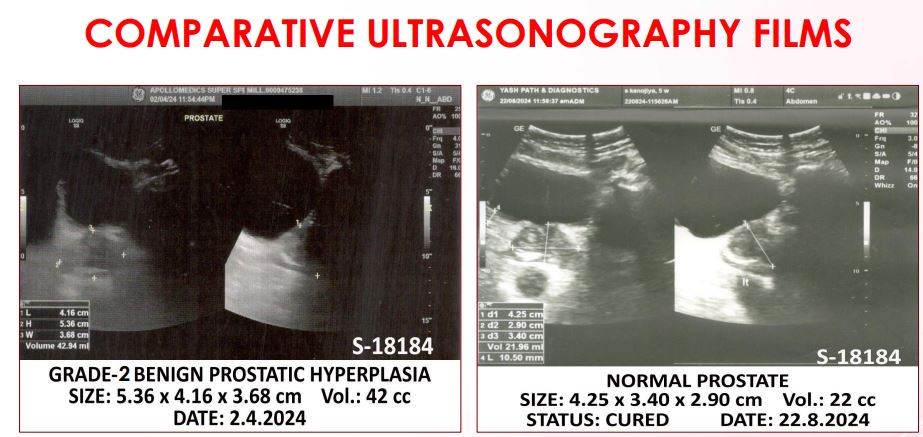

डॉ गिरीश ने बताया कि इन मरीजों में सबसे कम समय में नॉर्मल होने वाले मरीज का प्रोस्टेट 50 ग्राम का था जो कि 35 दिनों के इलाज के बाद 20 ग्राम का हो गया। इसी प्रकार सर्वाधिक आयु वाले मरीज की उम्र 98 वर्ष थी जिसका प्रोस्टेट 51 ग्राम का था, जो 100 दिनों के इलाज में 43 ग्राम आ गया। इसके अलावा सबसे बड़ा साइज का प्रोस्टेट जो 66 दिनों के उपचार के बाद नॉर्मल साइज का हो गया वह 60 ग्राम का था, इसके अतिरिक्त सबसे बड़े साइज का प्रोस्टेट जो उपचार के बाद नॉर्मल तो नहीं हुआ लेकिन कम हुआ वह 185 ग्राम का था जो कि कम होकर 151 ग्राम हो गया।